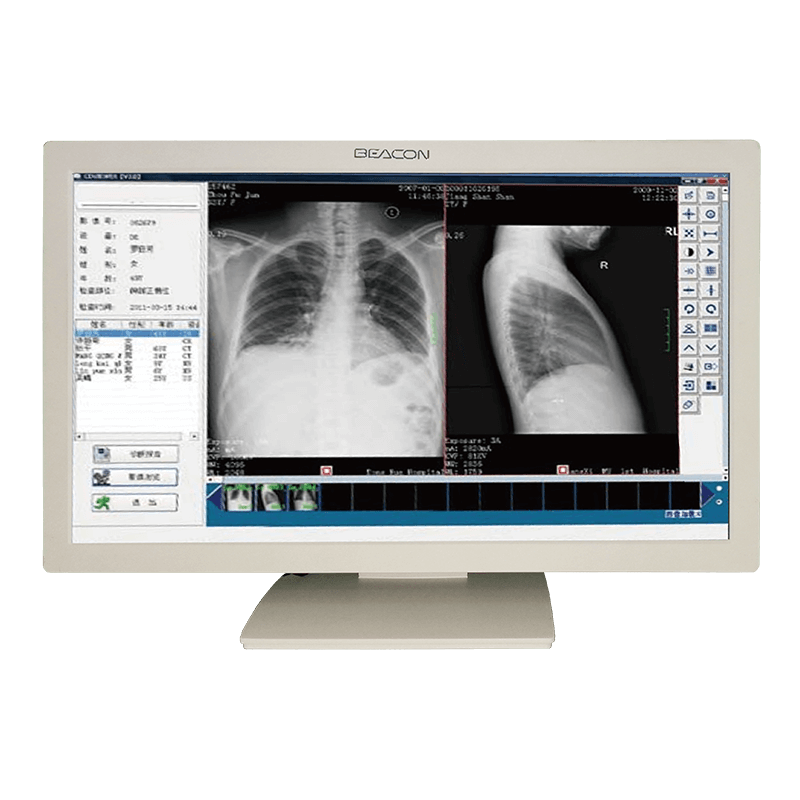

Полностью совместимый со стандартом DICOM и широкоформатным дизайном FHD,C22W может помочь врачам получить доступ к информации о пациентах в безфильмовой среде при просмотре различных медицинских изображений. Это может быть легко и легко, и повысить эффективность работы врачей и удовлетворенности пациентов.

Соответствие Стандарту DICOM

Медицинские изображения, включая самые тонкие детали, могут отображаться точно. Сохранить последовательность отображения между различными дисплеями, а также отображения и различных форм изображения, обеспечить точность диагностики.